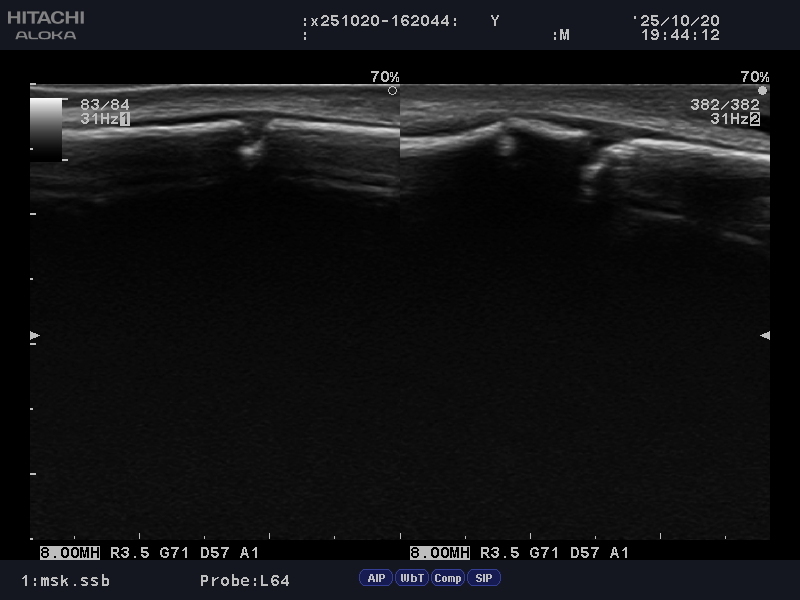

超音波検査では下記の様な像が見られました

骨折を伴う骨端線損傷と判断し

結果、予想通り骨折と診断。